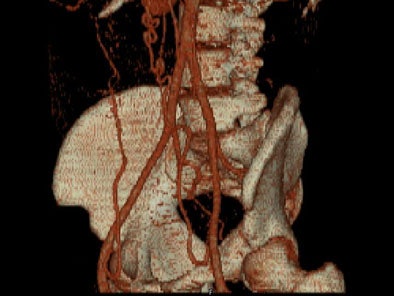

- On sagittal MIP images, the morphology of coarctation along with a captured left subclavian artery was demonstrated. Volume-rendered images showed hypertrophied internal mammary arteries and epigastric arteries. [Figures 3, 4, 5] [Movie 1]

|  |

| Figure 3. |

| Figure 4. |

| Figure 5. |